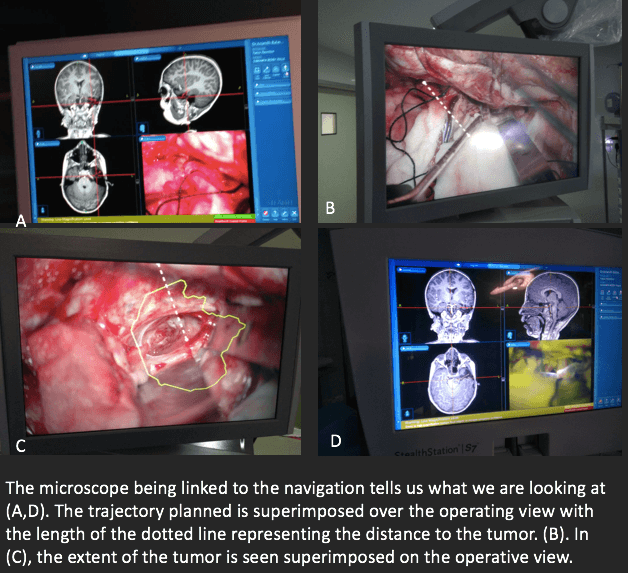

The MRI images were transferred to a navigation machine (Medtronic Stealth S7) that could track where we were at any point. While this seems a complicated explanation, the neuronavigation works like a GPS localization system. The MRI is the map, and the machine has 2 cameras that can localize special instruments in space, quite similar to way GPS satellites can pinpoint the location of our smartphones. This kind of technology has found application in brain and spine surgery making surgery today far safer than it was before.

This time we got the navigation machine to track the focus point of the microscope (Zeiss OPMI Pentero). This meant seamless workflow and rapid real-time confirmation of what was being looked at and where exactly that point was with respect to the MRI.

This is like two people looking at a map and one person knowing exactly where the other was looking without having to use a pointer.

Once all this was in place, the surgery began. The scalp was cut into and a window of bone removed to access the brain. A delicate, narrow corridor was created by dissecting between the lobes of the brain to see the glioma deep in the brain stem. This access was planned on the MRI and fed into the navigation machine. The machine in turn could overlay the plan and the glioma outline onto the microscope (since the two were linked) and make sure we were heading in the right direction.

Once we got to the surface of the glioma, all the intraoperative monitoring systems were checked and we could ensure that there were no nerves on the surface. But this tumor lay surrounded by nerves and cells that need to be preserved so our patients do well after surgery. And crucial distances in the brain are in millimetres or less. Thus when we knew we were looking at the surface of the glioma (both by what we saw and the navigation confirming what we were looking at) and we knew that the glioma was not surrounded by important nerves in that particular area (both by the preoperative MRI and the monitoring system), the next step was to delineate tumor from normal tissue.